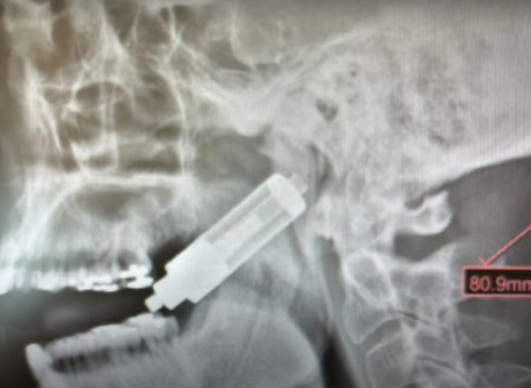

Vape explode e fica cravado em crânio de homem; veja imagem

Um homem ficou ferido após o vape em que ele fumava explodir e ficar cravado no crânio. O caso foi divulgado pela revista científica “oooo journal” no dia 11 de março, mas só viralizou nesta semana.

A identidade do paciente e o local onde aconteceu o incidente não foram revelado. De acordo com o estudo, o homem tragava a fumaça do cigarro eletrônico quando o dispositivo explodiu.

Com a pane no aparelho, o vape perfurou a garganta do paciente e ficou preso ao crânio.

“Lesões em tecidos moles e duros causadas por explosões de cigarros eletrônicos e seus projéteis envolvendo principalmente a região da cabeça e pescoço são tão reais quanto ferimentos por arma de fogo e acidentes automobilísticos”, explicou o professor Felipe Bravo, doutor e mestre em odontologia, nas redes sociais.